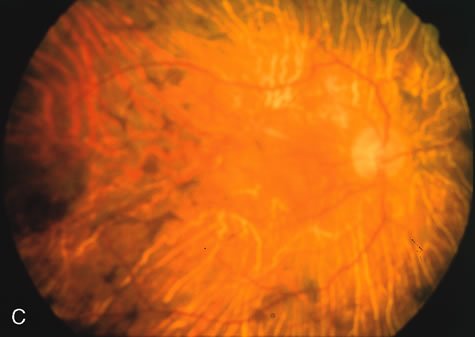

The fundus abnormalities in pigment pattern dystrophies may be subtle, especially when the pigmentary changes are orange and yellow in color. However, FA is most dramatic in highlighting these abnormalities. Thus, FA will confirm, and in some circumstances provide, the diagnosis (Fig. 11AE). Although there is no histopathologic confirmation, the fundus and angiogram suggest that an abnormal deposition of lipofuscin in the RPE is responsible for the clinical picture.

Fig. 11. Pigment pattern dystrophies. Subtle changes of the fundus in this family member with a pattern dystrophy (A) are highlighted on angiography (B). Equally dramatic is the fluorescein angiography of this young woman who presented with poor vision in association with a retinal hemorrhage (C). The angiogram reveals a bilateral, symmetric reticular pattern of the posterior pole (D, E).